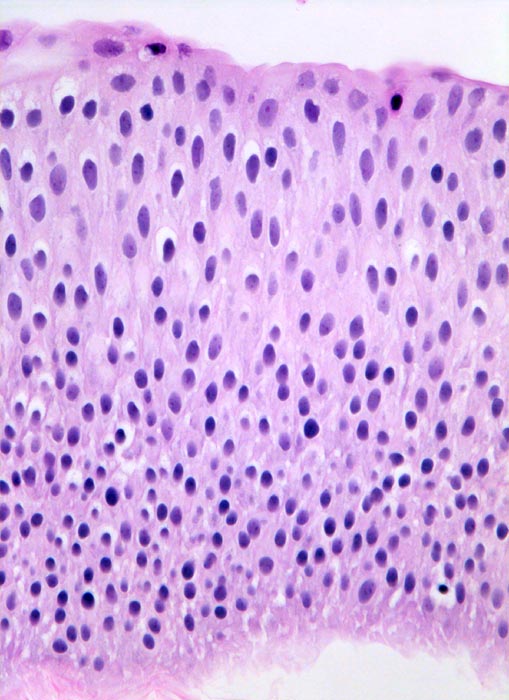

Bei den meisten papillären Urotheltumoren finden sich kleine Büschel von kubischen oder zylindrischen Urothelien. Die Kerne sind leicht vergrössert, oft spindelig und hyperchromatisch. Papilläre Karzinome mit leichter Epitheldysplasie sind aufgrund der sehr geringen Zellatypien in bis zu 50% der Fälle zytologisch nicht diagnostizierbar. Bei mässiger Epitheldysplasie sind die Urothelien polymorpher und hyperchromatischer.

Unten werden Beispiele von einem hoch differenzierten und drei mässig differenzierten papillären Karzinomen gezeigt.